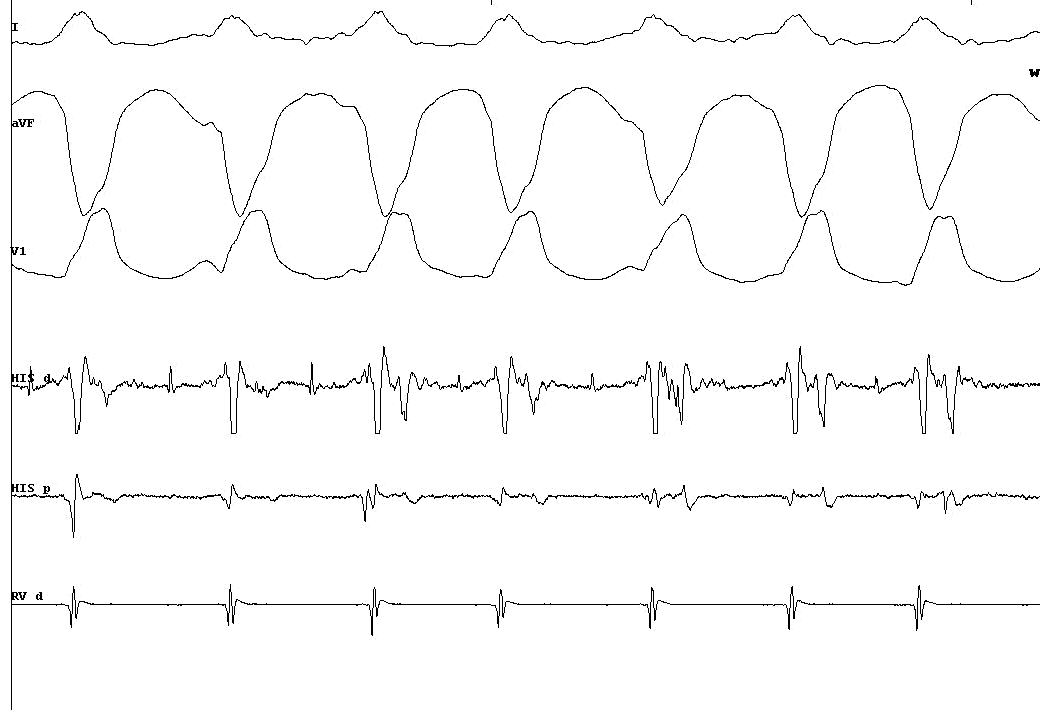

Tachy ECG

05_tachy_ecg.jpg